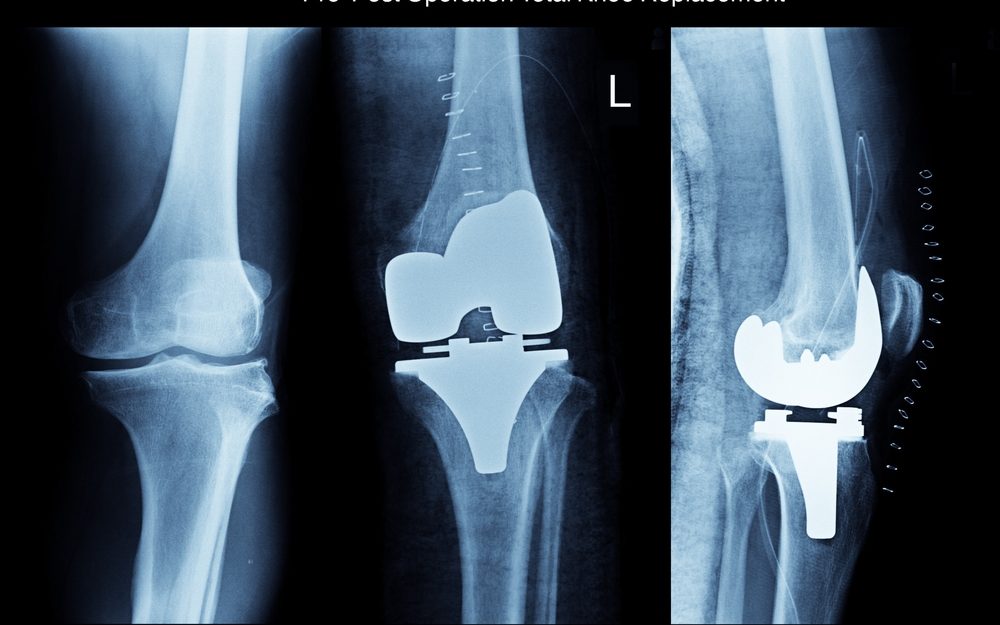

Debido al desgaste de las articulaciones de la rodilla ocasionado por la edad o la artrosis, en ocasiones se debe recurrir a una cirugía de reemplazo total de la articulación, por una artificial conocida como prótesis de rodilla. De esta manera, el cartílago y el hueso dañado se retira aliviando así el dolor intenso.

Una vez que se ha aplicado la anestesia, el cirujano hará una incisión sobre la rodilla, por lo general de 8 a 10 pulgadas d largo. Posteriormente:

Apartará la rótula y cortará los extremos del fémur y la tibia (parte inferior de la pierna) para acomodar la pieza de reemplazo.

Cortará la parte inferior de la rótula con el fin de prepararla para las nuevas piezas que irán pegadas allí.

Fijará las dos partes de la prótesis a los huesos. Una parte irá pegada al extremo del fémur y la otra irá fijada al extremo de la tibia.

Pegará ambas partes a la parte inferior de la rótula. Se usa un cemento óseo especial para pegar estas partes.

Reparará los músculos y tendones alrededor de la nueva articulación y cerrará la incisión quirúrgica.

Por lo general la duración de la cirugía de artroplastia de rodilla dura alrededor de 2 horas.